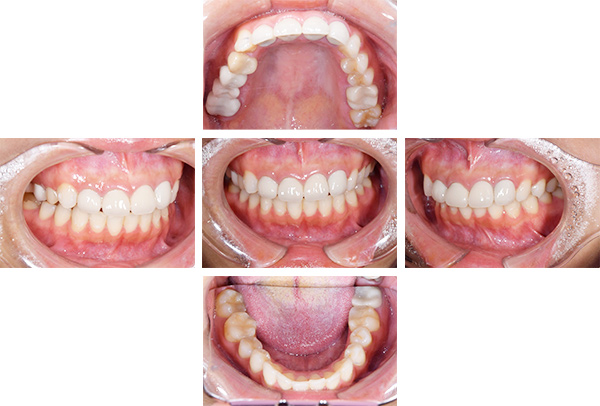

症例写真(治療後)

担当医師所見

矯正装置をつけています。だんだん八重歯が動いてきているのがわかります。今回のケースでは、抜歯を行わずに矯正ができました。

治療後:

矯正治療と虫歯の治療すべて終わったときの写真になります。見た目も最初の頃とは全く違いますし、お口の中もすごく綺麗です。

治療

方針

まずは虫歯の治療を行い、被せ物をする部分は仮歯をいれて矯正を行う。矯正終了後、仮歯の部分を最終的な被せ物に変えていく。また気になっていた銀歯もセラミックに変えて終了となった。

内容

セラミックインレー、オールセラミックプレミアム、矯正